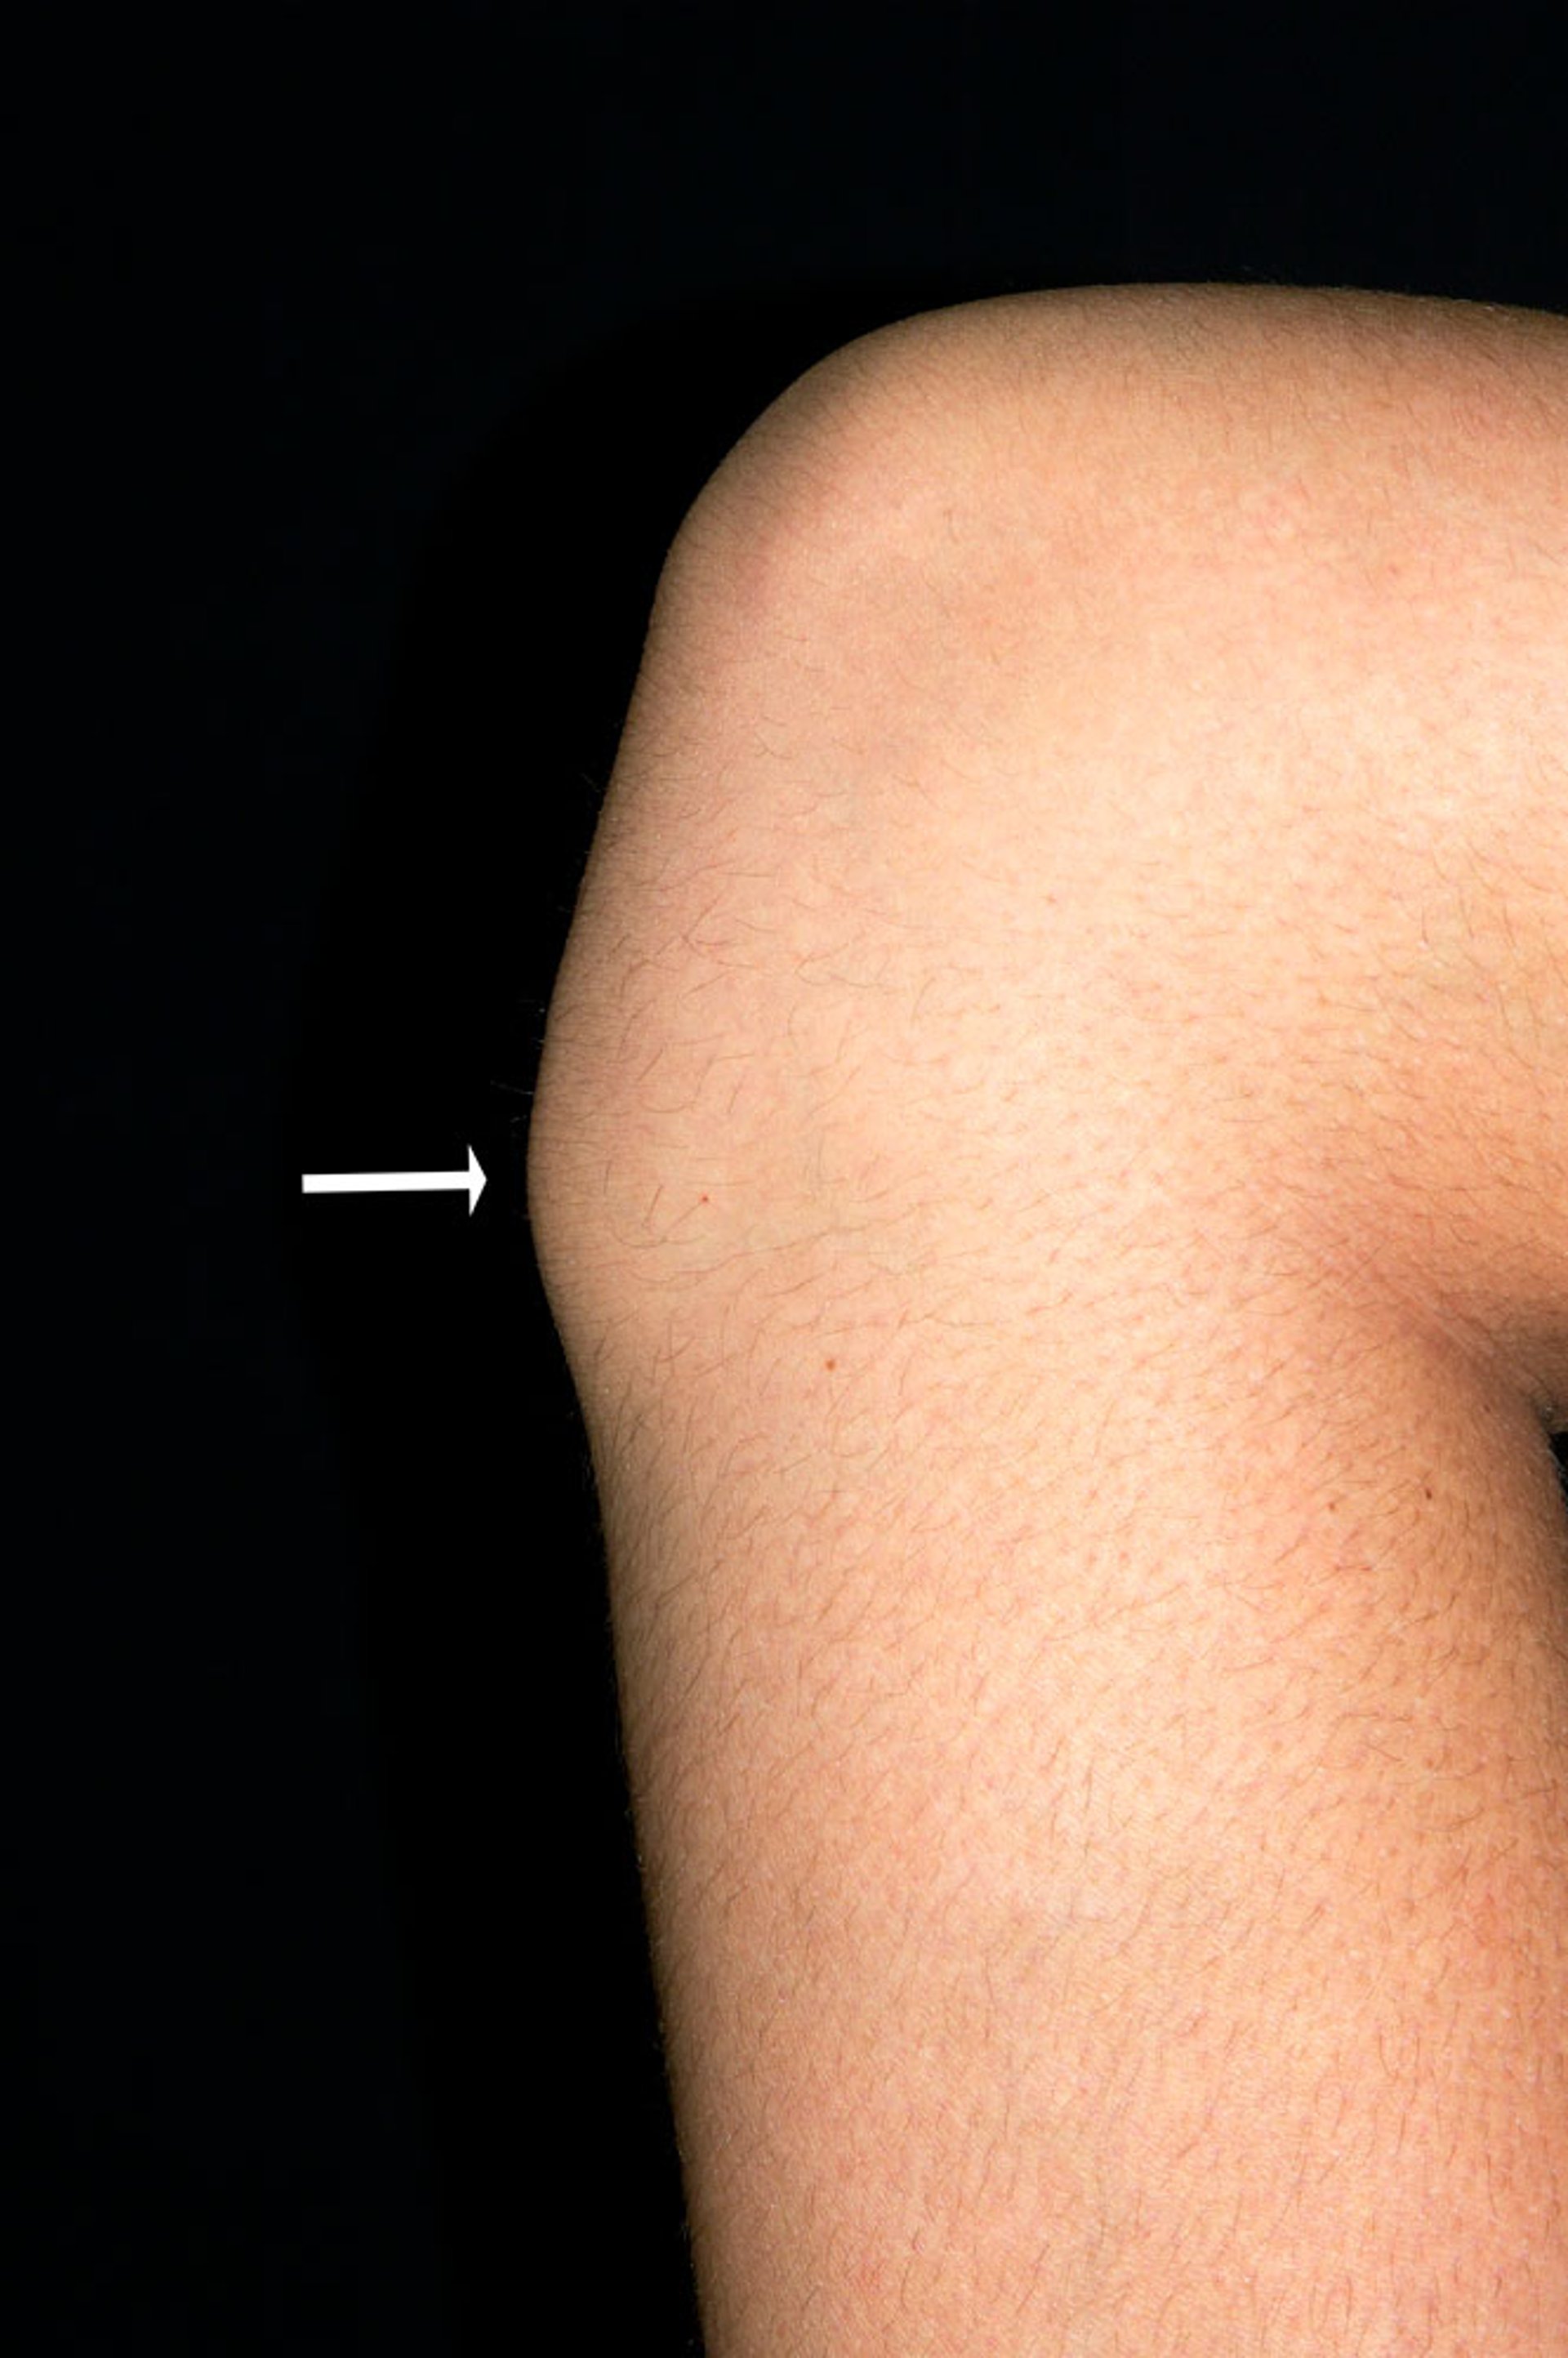

Tuberosidad tibial en la enfermedad de Osgood-Schlatter

Esta fotografía muestra la rodilla de un adolescente varón con una prominencia ósea (tuberosidad tibial, flecha) debido a la enfermedad de Osgood-Schlatter.